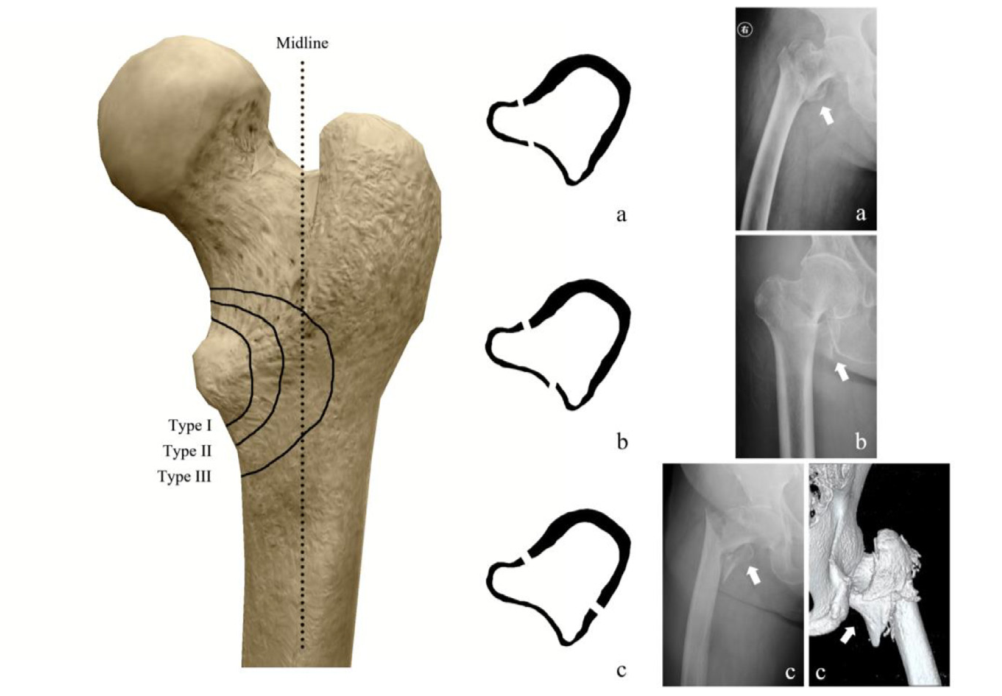

粗隆间骨折髓内固定失效,需要注意这一点!

粗隆间骨折好发于老龄患者,为三大骨质疏松性骨折之一,通常需采用内固定治疗。粗隆间骨折内固定的选择,与骨折类型密切相关。关于小转子及内侧壁的重要性,已经越来越受到重视,部分内固定的失效也与其相关。有学者研究了粗隆间骨折累及小转子及内侧壁的大小与内固定失效的关系,结果发表在Injury期刊上。